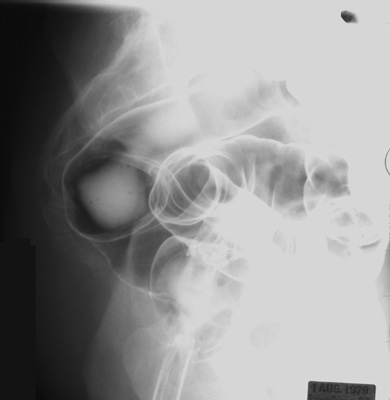

Lower the table to a horizontal position.

Roll the patient into the left lateral

position.

Lower the head of table down to -10 degrees.